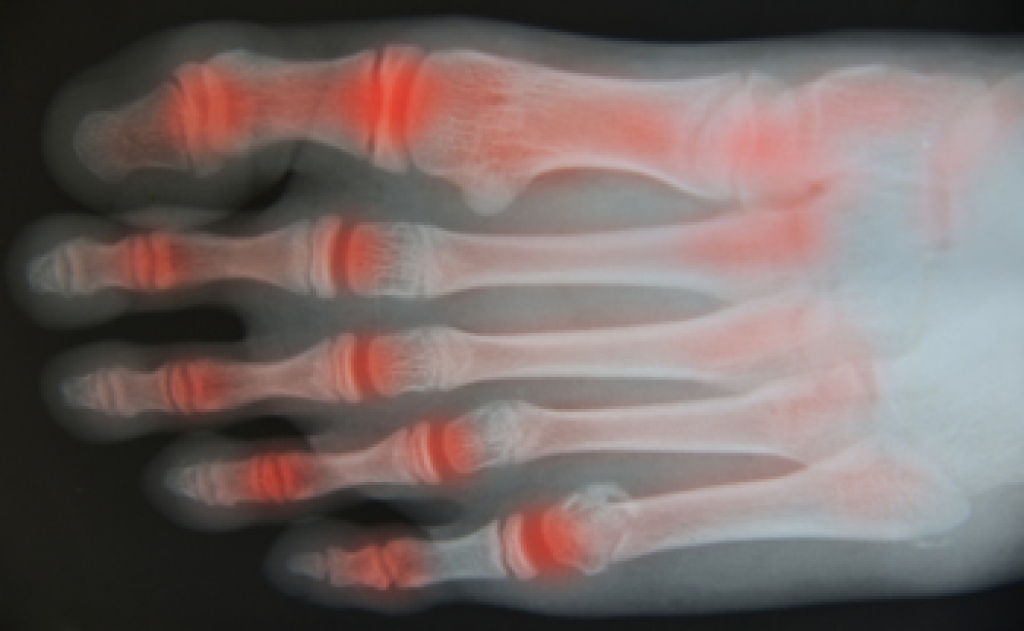

Arthritis is a joint disorder that involves the inflammation of different joints in your body, such as those in your feet. Arthritis is often caused by a degenerative joint disease and causes mild to severe pain in all affected areas. In addition to this, swelling and stiffness in the affected joints can also be a common symptom of arthritis.